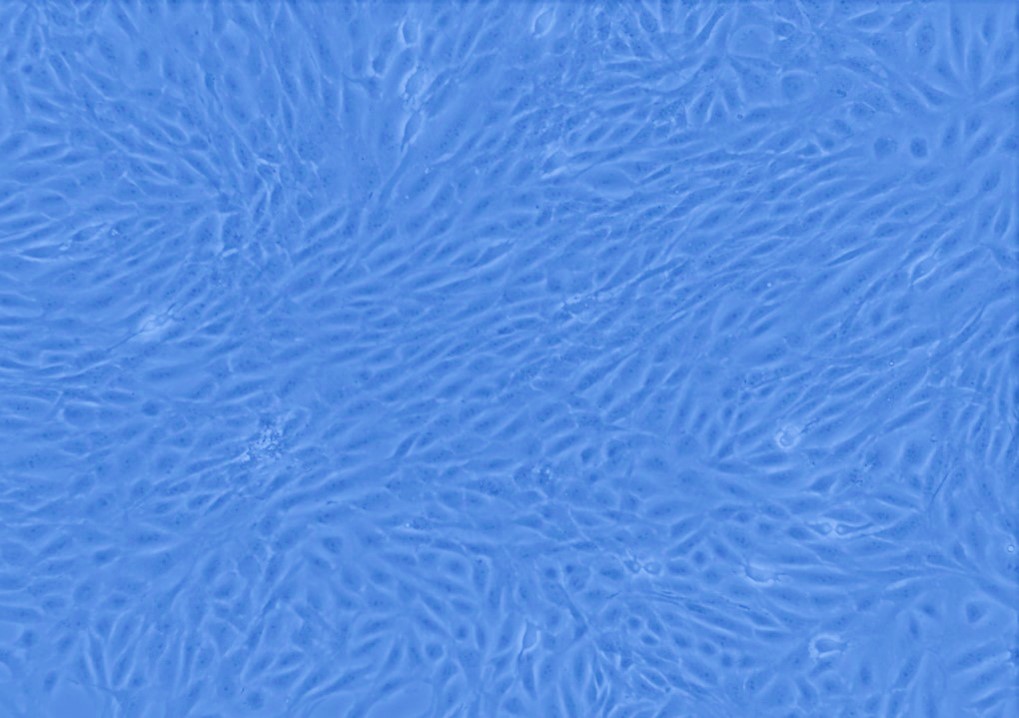

Culture Cellulaire